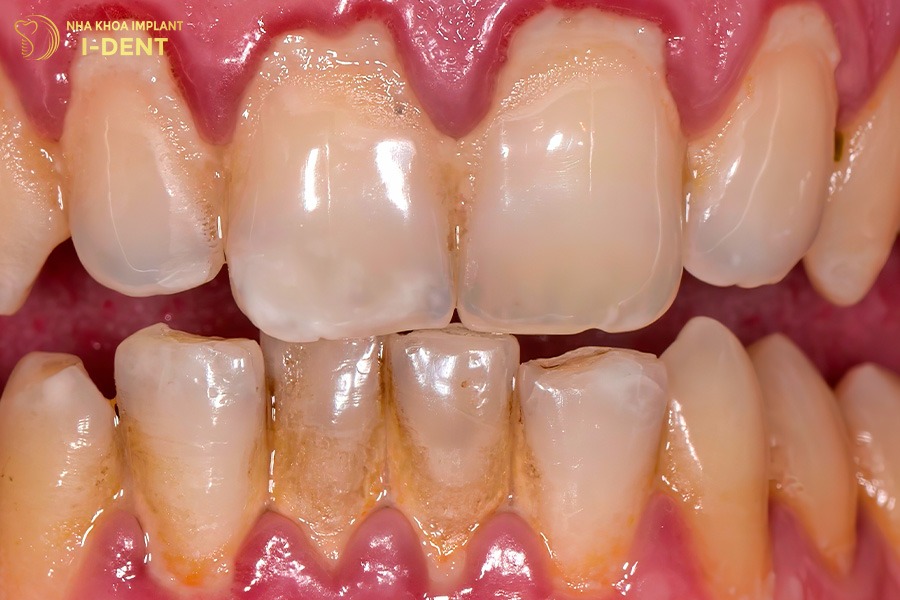

Một trong những nguyên nhân phổ biến khiến răng bị rụng sớm là do các bệnh lý răng miệng như viêm nướu và viêm nha chu. Khi mảng bám tích tụ lâu ngày, vi khuẩn sẽ tấn công mô nướu, phá hủy dây chằng và xương ổ răng làm răng bị lung lay, đau nhức và cuối cùng là mất răng.

Viêm nướu và nha chu là nguyên nhân hàng đầu dẫn đến rụng răng.